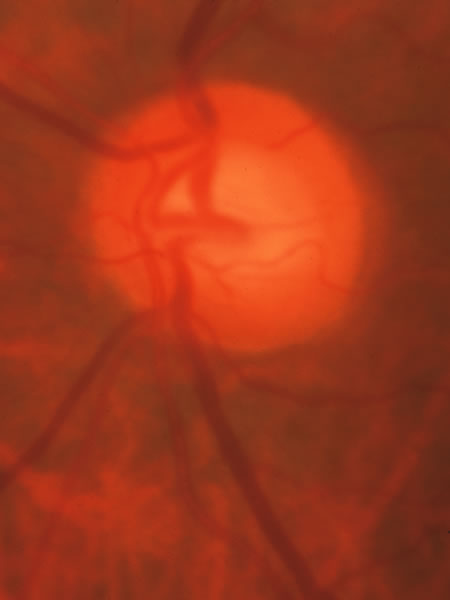

Usually all other forms of optic nerve disease (and inner retinal disease) produce simple atropy of the disc without cupping (Figs. 34 to 36), but occasional cases of cupping have been seen with anterior ischemic optic neuropathy, particularly due to giant cell arteritis (Figs. 37 and 38).

Fig. 34. Photograph of a normal left eye at a time when the right eye had an attack of anterior ischemic optic neuropathy.

Fig. 35. Same eye as Figure 34 during a subsequent attack of ischemic optic neuropathy.

Fig. 36. Same eye as in Figure 34 one year later, with atrophy but no excavation.